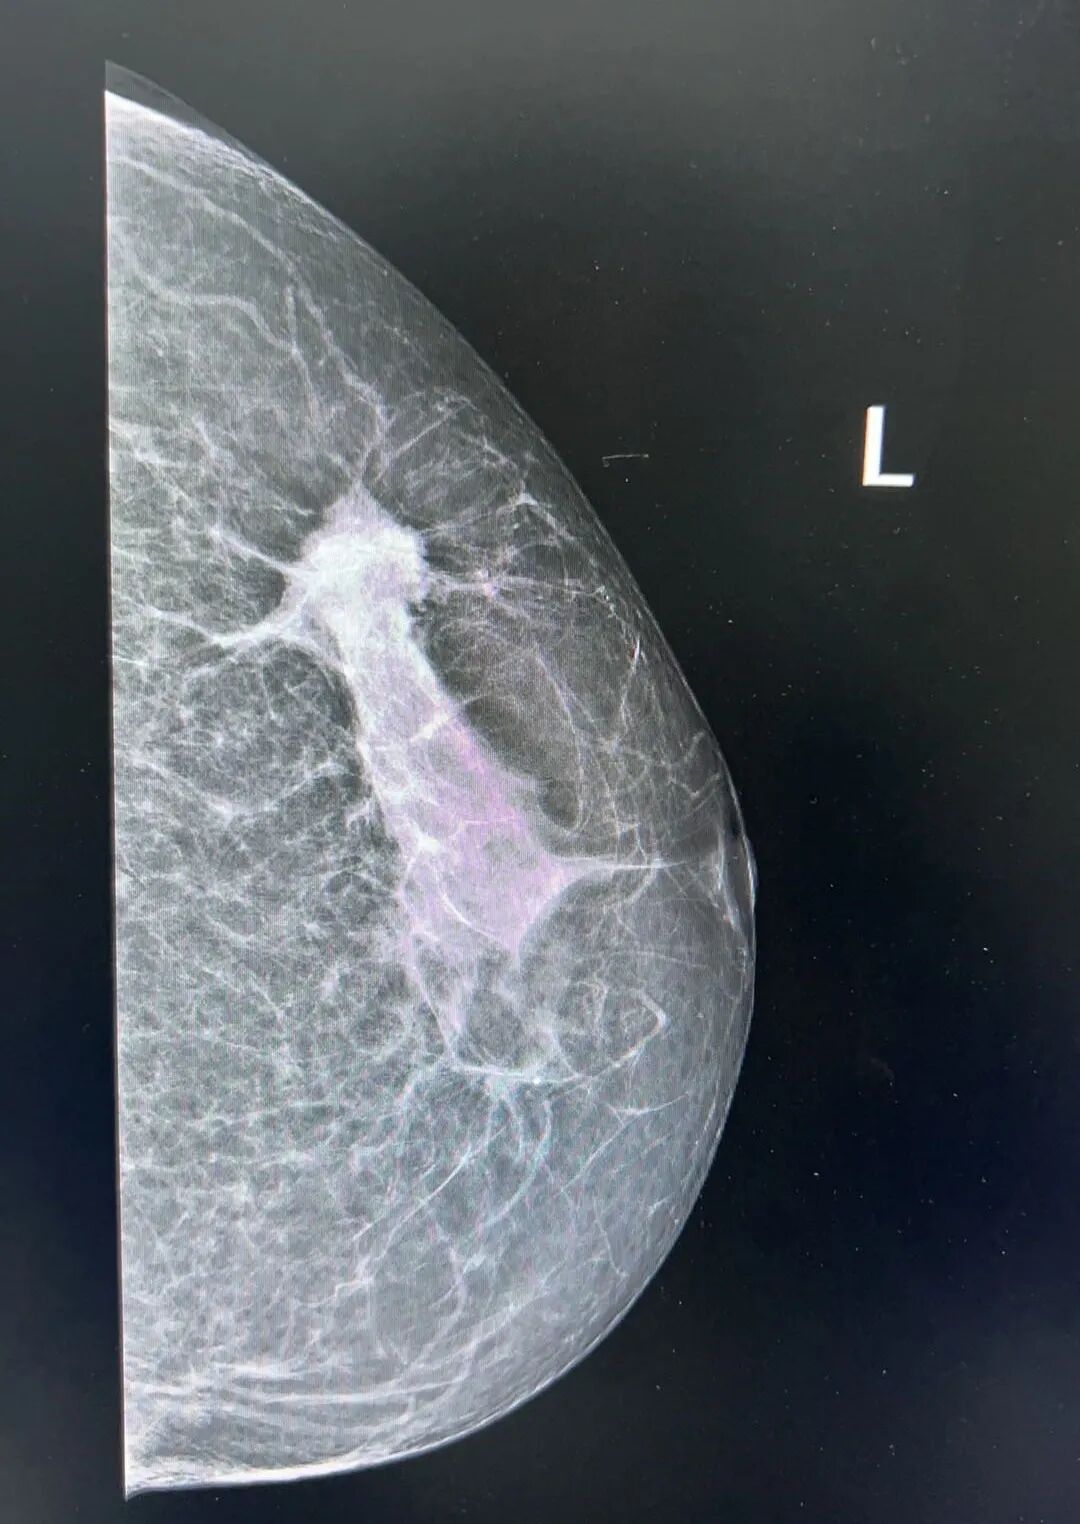

乳房与其它部位的最大不同之处,在于其完全由软组织构成,包括乳腺腺泡、腺管、结缔组织、脂肪、皮肤与皮下组织。这些组织彼此之间密度相近,缺乏天然对比,给乳腺的检查增加了困难。为了尽可能清晰地显示各种组织结构,对乳腺的X线常规检查条件要求很高,只有高清晰度的乳腺影像才能满足诊断上的要求。目前临床上广泛应用的钼靶X线技术,其诊断乳腺良恶性肿瘤正确率达85%-90%,并能发现触诊阴性的乳腺癌,早起筛查可以有效提高乳腺癌的检出率。因其放射量低,诊断率高,成为目前临床诊断和普查的一项不可缺少的诊断方法,也是诊断To期乳腺癌首选的检查方法。

乳腺钼靶,即为乳腺钼靶X线摄影检查,乳腺疾病的首选检查,具有简便、可靠、无创等优势。痛苦小,简便易行,分辨率高,重复性好,留取的图像可对比,不受年龄、体形的限制,已作为常规的检查。它的特点是可以检测出医生触摸不到的乳腺肿块和病理性钙化。对于以少许微小钙化为唯一表现的T0期乳腺癌(临床门诊阴性),也只能通过乳腺钼靶X线检查才能被早期发现和诊断,对乳腺癌的诊断敏感性为82%~89%,特异性为87%~94%。

两种检查各有所长,钼靶对于钙化灶极度敏感性,但钼靶影像为重叠影像,对致密性乳腺的效果相对较差,对乳房小结节的诊断准确率也不高,容易漏诊,此时需结合乳腺超声检查联合诊断。超声对肿块、硬度、血流信息获取量大。对钙化敏感性较低。因此,乳腺钼靶和超声称之为乳腺疾病检查的黄金组合,对于乳腺疾病的诊疗更精准。